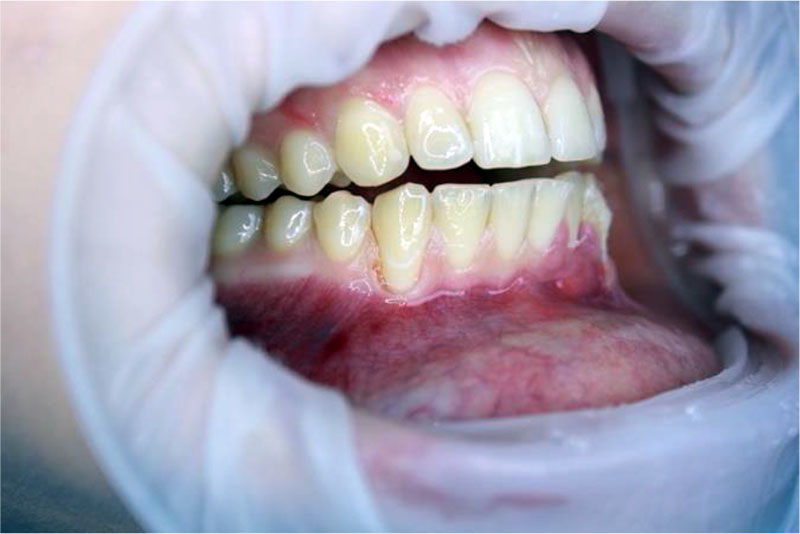

Patient A., 32 years old. Diagnosis: By 06.01 Recession of the gingiva, Miller class I. Local recession in the region of the 43 tooth (Fig. 3). The biotype of the gingiva is medium (1.0 mm), the gingival papillae are normal. Orthodontic treatment is planned. Preoperative treatment of the oral cavity was performed with 0.12% chlorhexidine solution for 1 minute. Under infiltration anesthesia Sol. Ultracaini D-S 1.7 ml performed an intrasulcular incision using a microsurgical scalpel (MANI, Japan). The exposed surfaces of the roots of the teeth were carefully processed to the height of the loss of clinical attachment in 4 stages: ultrasonic treatment, instrumental machining using Gracie Mini-Five curettes (Hu-Friedy, USA), polishing and smoothing of the tooth root surfaces using periodontal burs RA (Komet, Russia), drug treatment with the application of lincomycin hydrochloride 30 mg / ml for 2 minutes. Tunnel raspatory (Hu-Friedy, USA) exfoliated the mucous split flap and prepared the tunnel bed. A free gingival autograft was taken from the hard palate (Fig. 4) and its de-epithelization (Fig. 5), adapted in size and introduced into the tunnel bed using guides positioning sutures PTFE 5.0 (Golnit, Russia) (Fig. 6). The wound was sutured using double twisted sutures PTFE 5.0 (Golnit, Russia) (Fig. 7). Postoperative drug treatment was performed with 0.12% chlorhexidine solution. Removal of stitches after 14 days. The result after 1 month is the complete elimination of gingival recession in the area of tooth 43, but unevenness of the keratinized gingiva is observed in the area of the base of the interdental papillae (Fig. 8).

Figure 3. Local recession of class I according to Miller in the region of the 43 tooth.